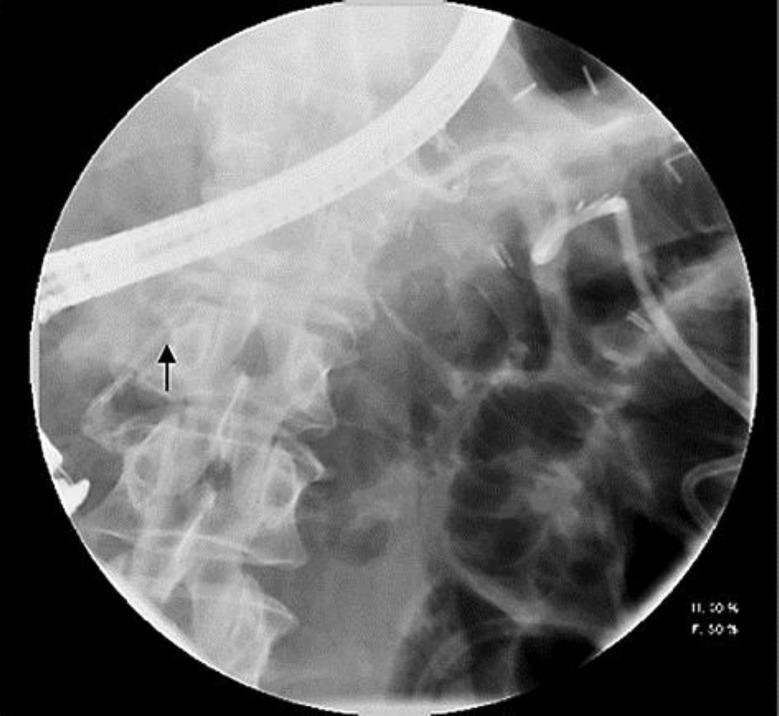

Pancreatic fistula is a known complication of distal pancreatectomy. Endotherapy with pancreatic duct stent placement and pancreatic sphincterotomy has been shown to be effective in its management; however, experience of endotherapy in the management of this complication has not been extensively reported from the United States. Preoperative endoscopic retrograde cholangiopancreatography (ERCP) with pancreatic stent placement has also been proposed to prevent this complication after distal pancreatectomy. In our cohort of 59 patients who underwent distal pancreatectomy, 13 (22%) developed a pancreatic fistula in the immediate postoperative period, of whom 8 (14%) patients (5 female, mean age 52 years) were referred for an ERCP because of ongoing symptoms related to the pancreatic fistula. The pancreatic fistula resolved in all patients after a median duration of 62 days from the index ERCP. The median number of ERCPs required to document resolution of the pancreatic fistula was 2. Although a sizeable percentage of patients develop a pancreatic fistula after distal pancreatectomy, only a small percentage of patients require ERCP for management of this complication. Given the high success rate of endotherapy in resolving pancreatic fistula and the fact that the majority of patients who undergo distal pancreatectomy never require an ERCP, performing ERCP for prophylactic pancreatic duct stent prior to distal pancreatectomy might not be necessary.

胰瘘是胰体尾切除术已知的并发症。胰管支架置入和胰管括约肌切开术的内镜治疗已被证明对其治疗有效;然而,美国尚未广泛报道内镜治疗该并发症的经验。术前内镜逆行胰胆管造影(ERCP)并放置胰管支架也被提议用于预防胰体尾切除术后的这种并发症。在我们的59例接受胰体尾切除术的患者队列中,13例(22%)在术后即刻发生了胰瘘,其中8例(14%)患者(5例女性,平均年龄52岁)因与胰瘘相关的持续症状而接受ERCP检查。自首次ERCP起,所有患者的胰瘘在中位时间62天后均得到解决。记录胰瘘解决所需的ERCP中位次数为2次。尽管相当比例的患者在胰体尾切除术后发生胰瘘,但只有一小部分患者需要ERCP来处理这种并发症。鉴于内镜治疗解决胰瘘的成功率很高,且大多数接受胰体尾切除术的患者从未需要ERCP,在胰体尾切除术前行ERCP预防性放置胰管支架可能没有必要。